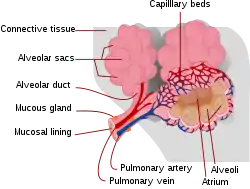

Pulmonary contusion and laceration are injuries to the lung tissue. Pulmonary laceration, in which lung tissue is torn or cut, differs from pulmonary contusion in that the former involves disruption of the macroscopic architecture of the lung,[1] while the latter does not.[2] When lacerations fill with blood, the result is pulmonary hematoma, a collection of blood within the lung tissue.[3] Contusion involves hemorrhage in the alveoli (tiny air-filled sacs responsible for absorbing oxygen), but a hematoma is a discrete clot of blood not interspersed with lung tissue.[4] A collapsed lung can result when the pleural cavity (the space outside the lung) accumulates blood (hemothorax) or air (pneumothorax) or both (hemopneumothorax). These conditions do not inherently involve damage to the lung tissue itself, but they may be associated with it. Injuries to the chest wall are also distinct from but may be associated with lung injuries. Chest wall injuries include rib fractures and flail chest, in which multiple ribs are broken so that a segment of the ribcage is detached from the rest of the chest wall and moves independently.

In contusions, torn capillaries leak fluid into the tissues around them.[33] The membrane between alveoli and capillaries is torn; damage to this capillary–alveolar membrane and small blood vessels causes blood and fluids to leak into the alveoli and the interstitial space (the space surrounding cells) of the lung.[11] With more severe trauma, there is a greater amount of edema, bleeding, and tearing of the alveoli.[17] Pulmonary contusion is characterized by microhemorrhages (tiny bleeds) that occur when the alveoli are traumatically separated from airway structures and blood vessels.[24] Blood initially collects in the interstitial space, and then edema occurs by an hour or two after injury.[30] An area of bleeding in the contused lung is commonly surrounded by an area of edema.[24] In normal gas exchange, carbon dioxide diffuses across the endothelium of the capillaries, the interstitial space, and across the alveolar epithelium; oxygen diffuses in the other direction. Fluid accumulation interferes with gas exchange,[34] and can cause the alveoli to fill with proteins and collapse due to edema and bleeding.[24] The larger the area of the injury, the more severe respiratory compromise will be.[17]

Ventilation/perfusion mismatch

Normally, the ratio of ventilation to perfusion is about one-to-one; the volume of air entering the alveoli (ventilation) is about equal to that of blood in the capillaries around them (perfusion).[40] This ratio is reduced in pulmonary contusion; fluid-filled alveoli cannot fill with air, oxygen does not fully saturate the hemoglobin, and the blood leaves the lung without being fully oxygenated.[41] Insufficient inflation of the lungs, which can result from inadequate mechanical ventilation or an associated injury such as flail chest, can also contribute to the ventilation/perfusion mismatch.[31] As the mismatch between ventilation and perfusion grows, blood oxygen saturation is reduced.[41] Pulmonary hypoxic vasoconstriction, in which blood vessels near the hypoxic alveoli constrict (narrow their diameter) in response to the lowered oxygen levels, can occur in pulmonary contusion.[27] The vascular resistance increases in the contused part of the lung, leading to a decrease in the amount of blood that flows into it,[38] directing blood to better-ventilated areas.[27] Although reducing blood flow to the unventilated alveoli is a way to compensate for the fact that blood passing unventilated alveoli is not oxygenated,[27] the oxygenation of the blood remains lower than normal.[40] If it is severe enough, the hypoxemia resulting from fluid in the alveoli cannot be corrected just by giving supplemental oxygen; this problem is the cause of a large portion of the fatalities that result from trauma.[41]